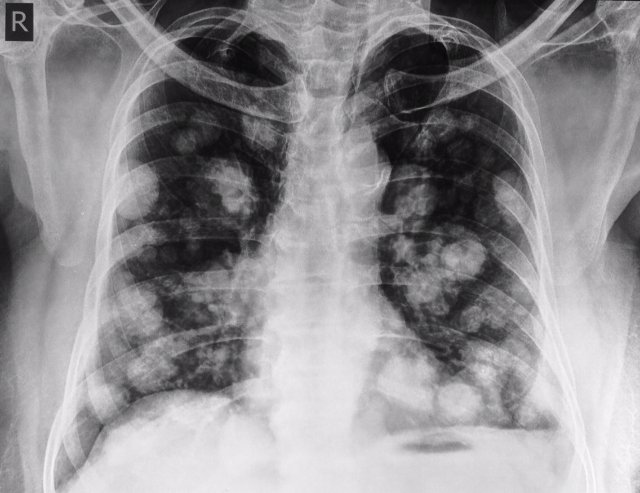

El signe radiogràfic: "bales de canó"

Metàstasi a pulmon. És clàssic veure el signe com a "bales de canó". Càncer de mama i còlon els mes freqüents.